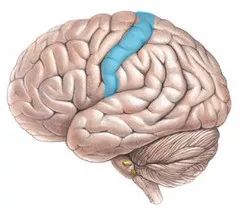

额叶还负责你身体的运动,额叶最上面的一带,是你的运动皮质。

接着是顶叶(parietal lobe) ,顶叶控制触觉,这一部分功能主要在体感皮质实现,体感皮质在运动皮质旁边。

运动和体感皮质很有趣,因为它们和人体的对应关系非常工整。神经科学家清哪楚地知道每个皮质的各部位分别对应身体的那些部分,下面我们要放出本文中最奇怪的一张图:何蒙库鲁兹(homounculus)

何蒙库鲁兹由神经外科医生Wilder Penfield创造,用来呈现运动和触感皮质如何对应到人体部位。图中的人体部位越大,代表运动和触感皮质中有越多的部分是与该部位对应的。这张图有一些有趣的点:

首先,皮质中负责脸和手的运动和触感的部分,比全身其它部分加起来都要大。当然这不难想通,人脸需要能做出各种微妙的表情,而手需要能够无比的灵巧。而身体的其它部位,比如肩膀、膝盖、背部,在移动和触感上可以粗糙很多。所以人们用手指,而不是脚趾,来弹钢琴。

其次,运动和触觉皮质各自对于不同身体部位的分配比例基本是一致的。也就是说人体中越是需要灵活运动的部位,也越是触觉最灵敏的。